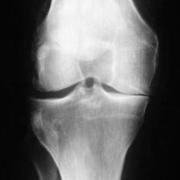

A varus thrust is the result of a meniscectomy on the medial side, closing the X-ray gap that normally exists because of the radiolucent meniscus that normally fills the gap. Eventually the ligaments can stretch and bow-leggedness becomes permanent rather than only occuring on weight-bearing.